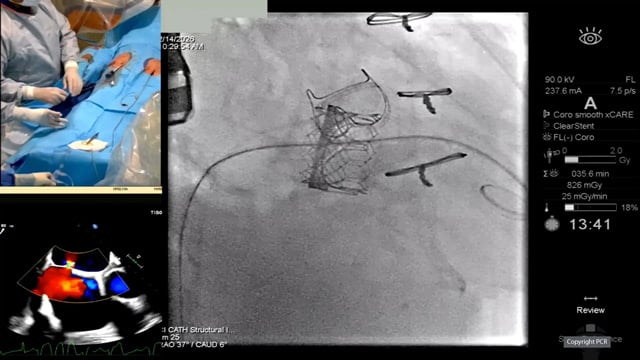

Mitral and aortic transcatheter valve-in-valve intervention - LIVE case

14 Feb 2026 – From PCR Tokyo Valves 2026

Live case

An 83-year-old male with AF, CKD (stage 3A), preserved LV function, and a history of AVR (27 mm Magna Ease) and MVR (33 mm Magna) in 2014 presented with symptomatic stenosis of the mitral bioprosthesis. A Sapien 3 valve was implanted in the Magna mitral...